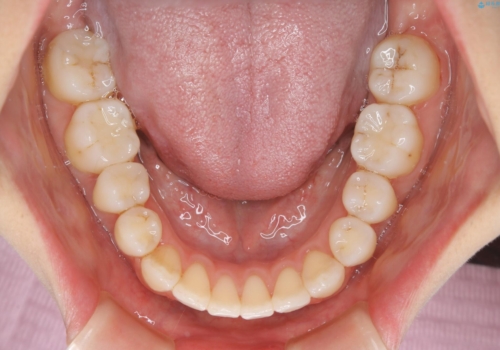

非抜歯、ワイヤーでの矯正治療。歯のがたつき、顎のズレ、出っ歯を治す。インビザラインが使えない方

- 歯のガタつき、顎のズレ、出っ歯を気にして来院された患者様です。

歯を抜きたくないとの希望であったためマウスピース治療をお勧めしましたが、

マウスピースをずっとつけていることは難しいとの事であったためワイヤー矯正治療を行うこととなりました。